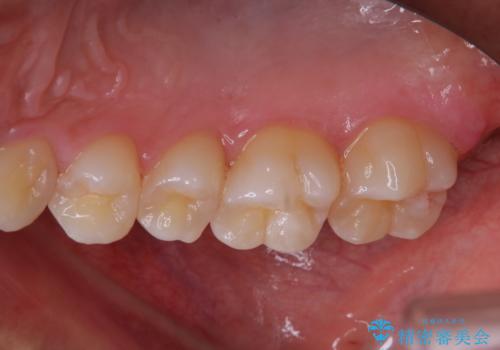

今後、ホームホワイトニング予定との事で、クリーニングPMTC(保険適応外)60分コースを行いました。汚れを取り除き、ご自身の本来の歯の表面になることでツヤがでます。

歯の表面に汚れがついたままホワイトニングを行うと、ホワイトニングの効果が出づらいことがあります。

ホワイトニングご希望の場合は、まずクリーニングを行うことをおすすめします。